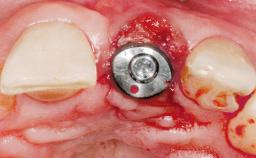

Late Placement of an Implant in a Maxillary Left Central Incisor Site

Type of Implants One-Piece|Reduced-Diameter

Attachment One-Piece|Reduced-Diameter

Bone Volume Deficient horizontally, requiring prior grafting